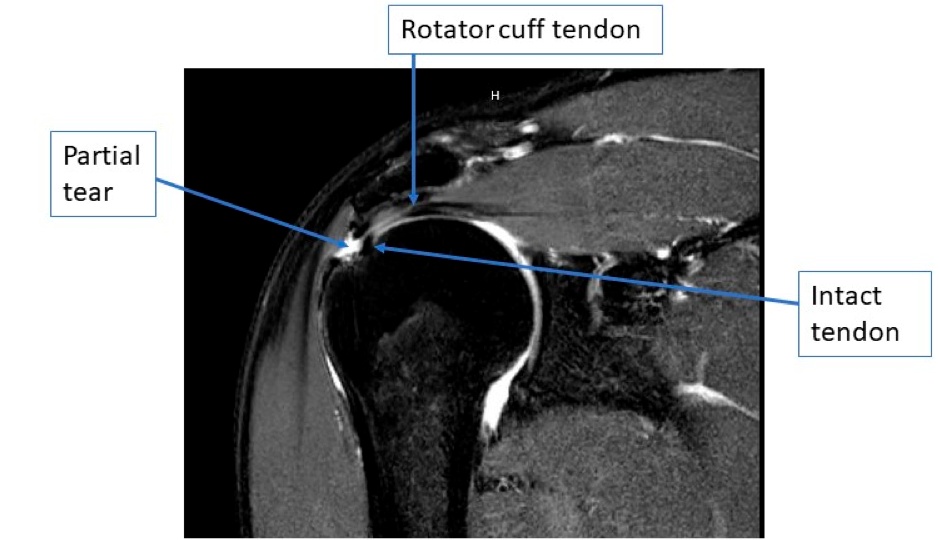

Partial Thickness Rotator Cuff Tears

A partial thickness rotator cuff tear involves only a portion of the rotator cuff fibers being torn, with some still being attached to the proximal humerus. These tears can be treated without surgery initially, which typically involves physical therapy, activity modifications, NSAIDs, and sometimes cortisone injections. When non-operative treatments fail to alleviate pain, then surgery can be performed.

PASTA MRI

A coronal MRI image of a partial, bursal sided rotator cuff tear.